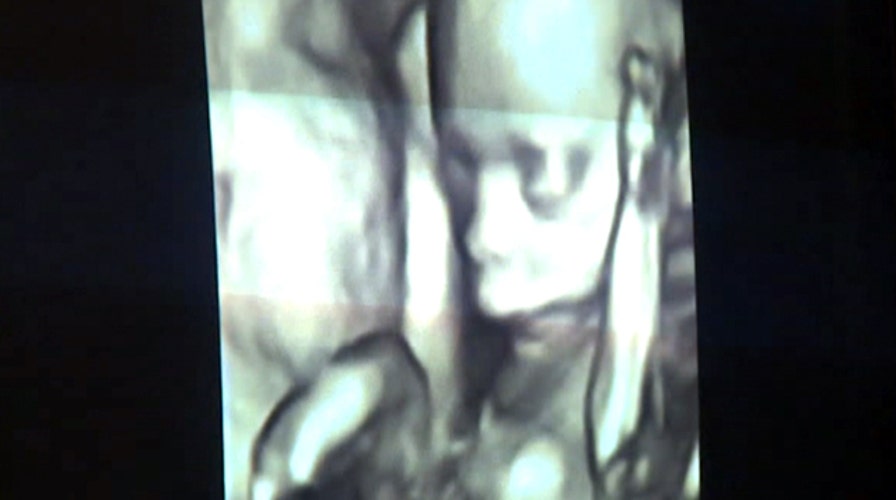

Keepsake industry has exploded